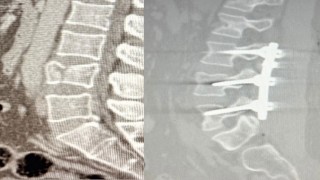

Bel kayması sebebiyle yürümekte zorlanıyordu, ameliyatla sağlığına kavuştu

28-07-2025 16:25

Ağrı'nın Patnos Ilçesinde, Bel Omurlarındaki Kayma Nedeniyle Yıllardır Yürümekte Zorlanan Kadın, Pat...

Yüksekten düşen hasta, Patnosta ilk kez uygulanan ameliyatla ayağa kalktı

28-07-2025 16:02

Ameliyat Sırasında Bel Bölgesindeki Omurların Sabitlenmesini Sağlayan Lomber Stabilizasyon Tekniği K...